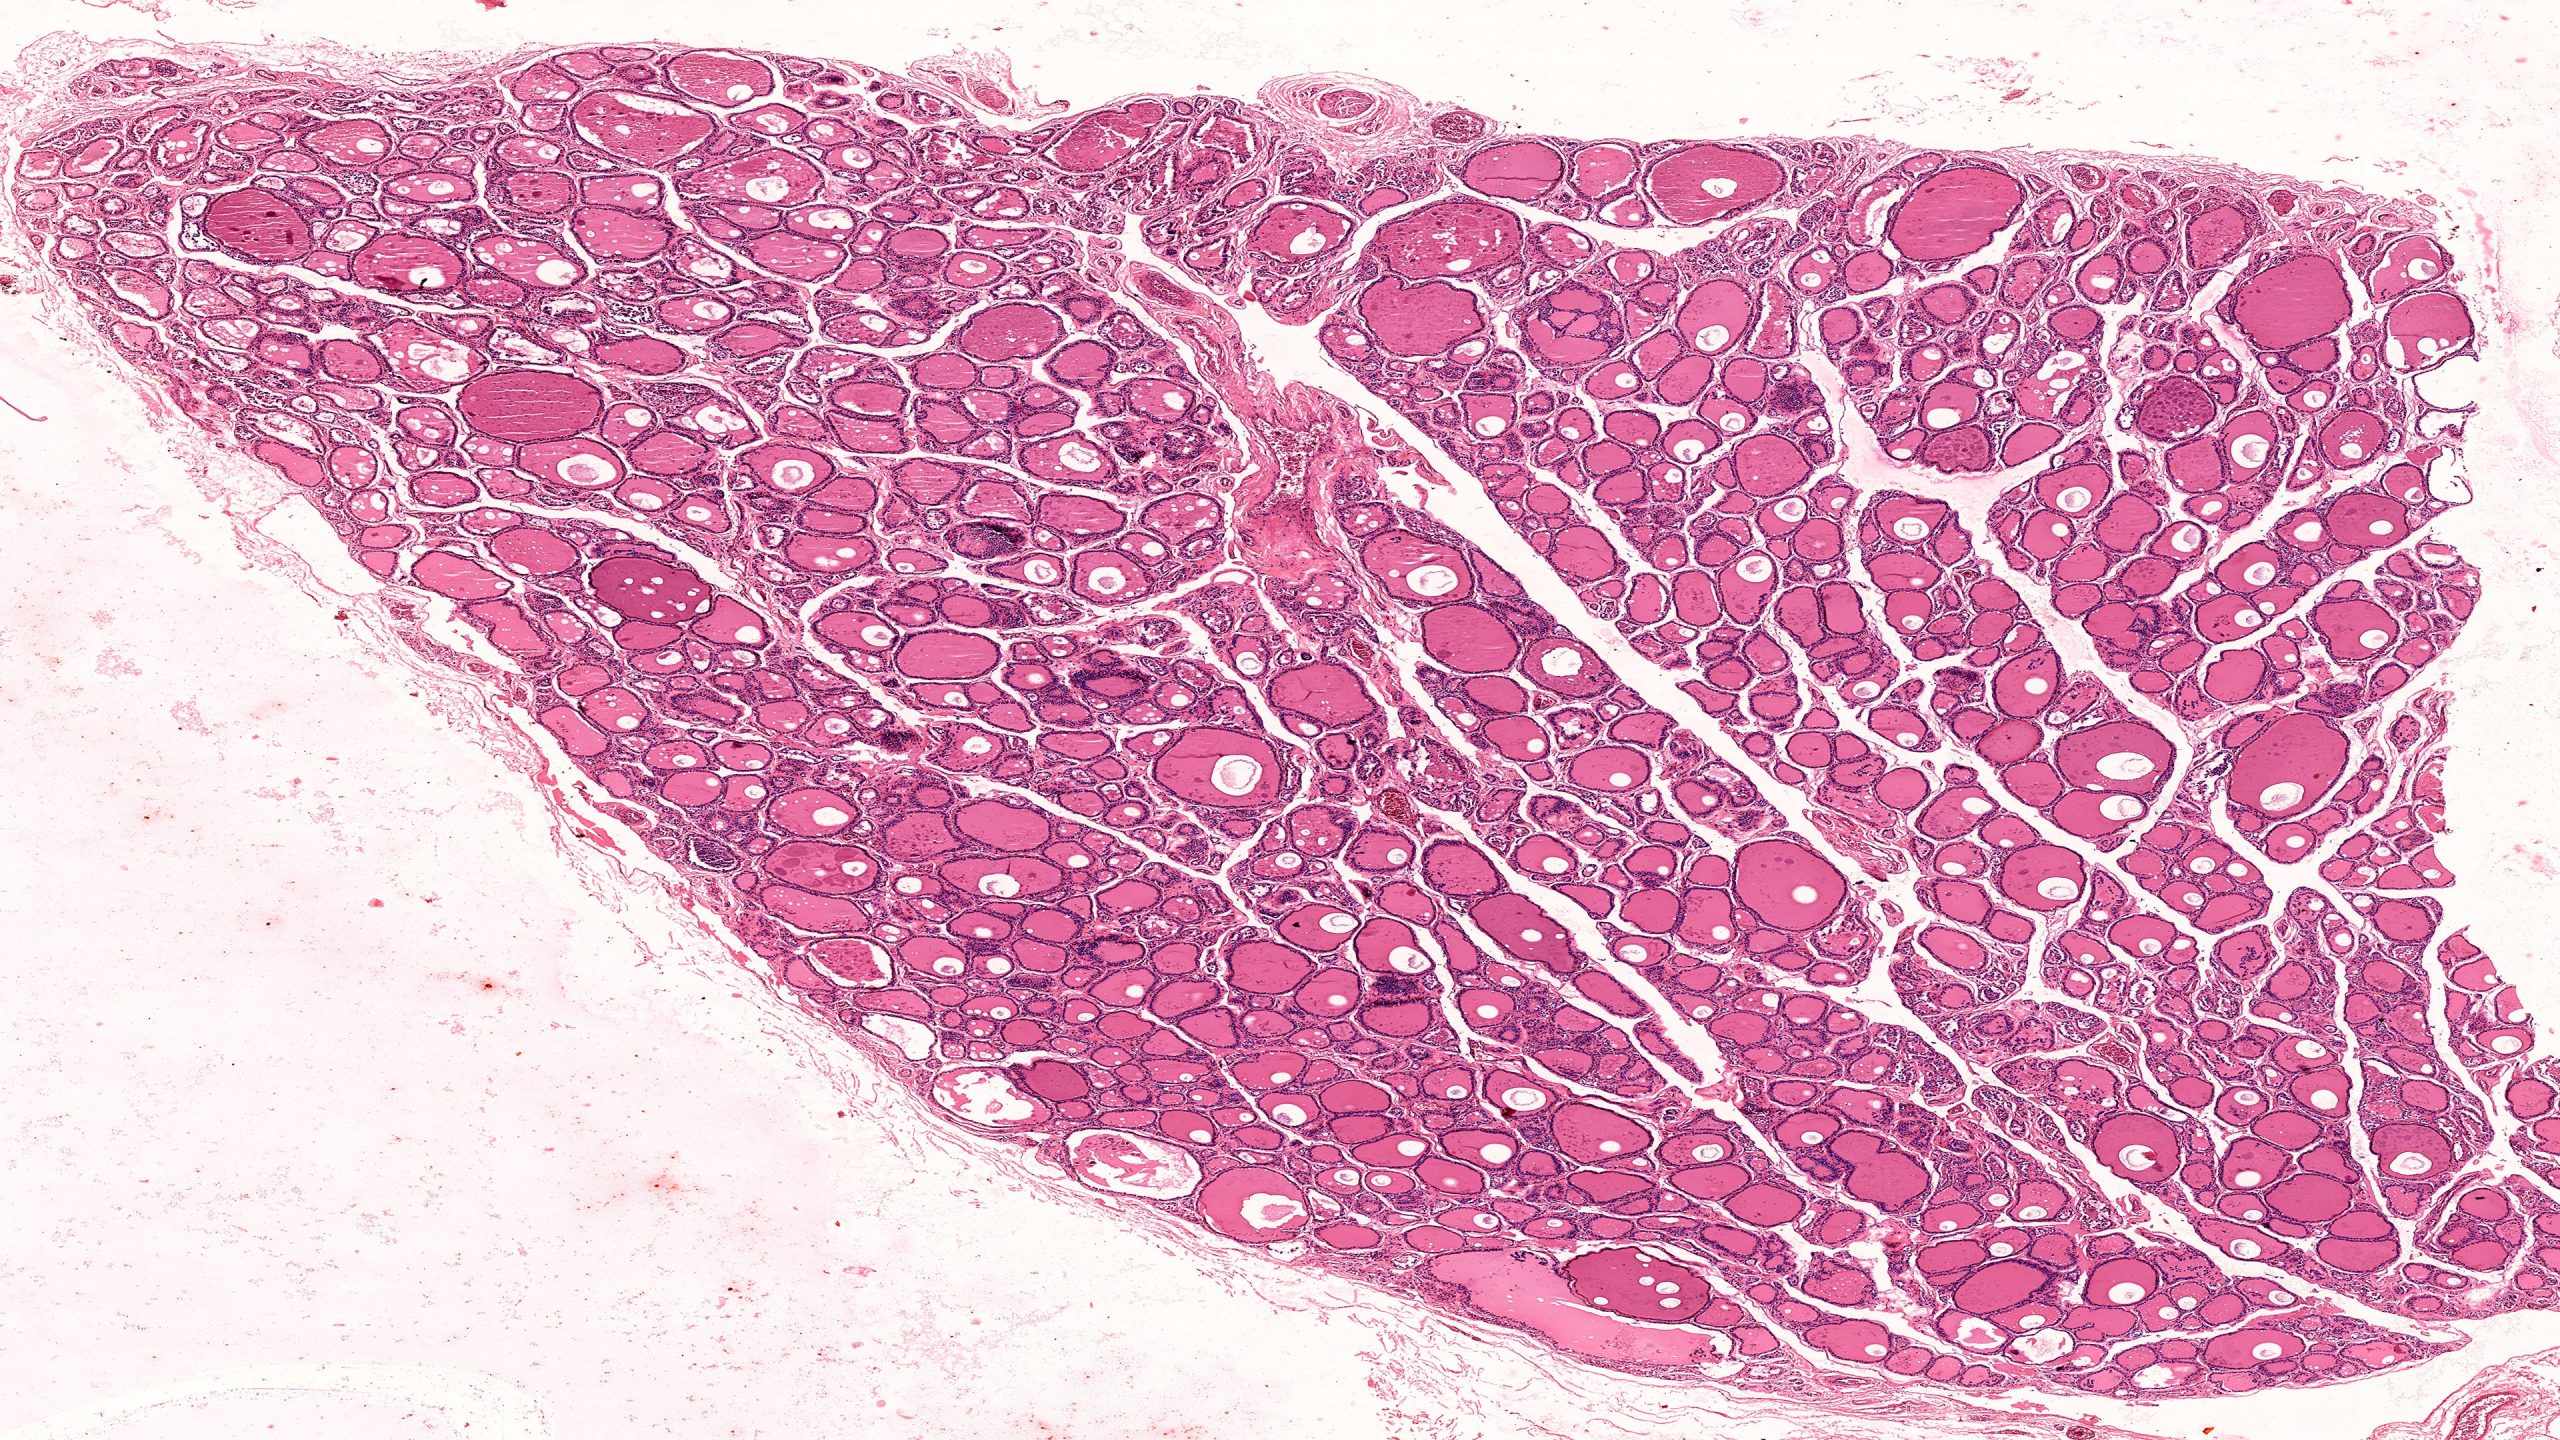

Thyroid and Parathyroid 4X